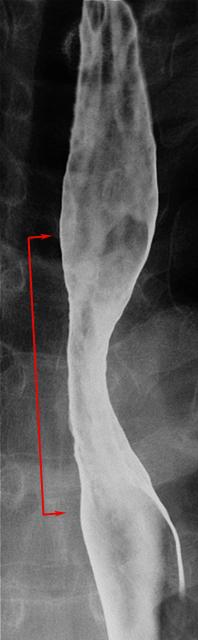

clasificación del pacienteTumor Epitelial Maligno/Carcinoma a Células Escamosas

parte(separada por órganos)esófago/medio

método de exámenRayos X

clasificación ectoscópica de tumoresTipo 0(tipo superficial)/Tipo IIc(IIc)

diámetro mayor del tumor40 -

grado de penetraciónm